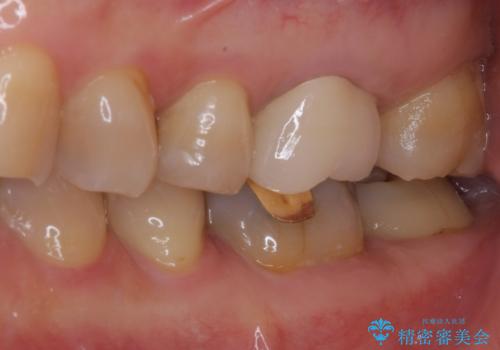

境目にものが詰まって気になる オールセラミッククラウン治療

- 奥歯に装着したクラウンの周りに汚れが溜まりやすいとのことで来院された患者様です。

既に装着されているクラウンの質は決して悪いものではありませんでしたが、患者様自身が非常に気にしていたため、作り替えの治療を行うこととしました。

クラウン装着後は、特にものが挟まる感覚もなく、快適に過ごすことができるようになりました。